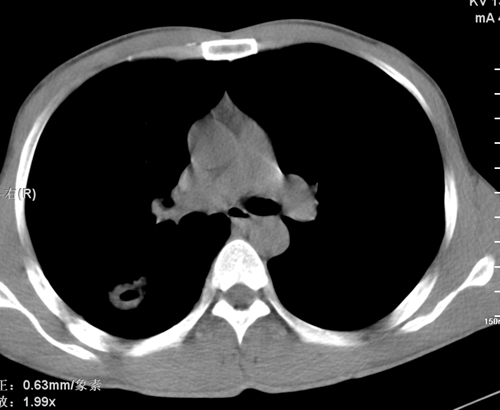

标题: CT24548:男 31 咳嗽 咯血一天 行CT检查 [打印本页]

标题: CT24548:男 31 咳嗽 咯血一天 行CT检查

ct考虑结核 但化验结果示白细胞总数 淋巴均正常,血沉7mm/h不快,请看看结核 支扩还是其他

右肺上叶尖端,后段下叶背段结核伴空洞形成

右肺继发性肺结核伴空洞形成!

右肺继发性肺结核伴右肺下叶背段空洞形成。